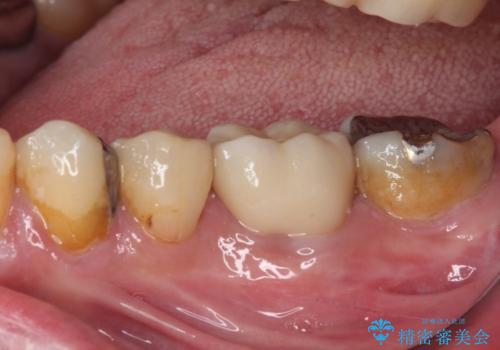

- 根っこの一部だけになった歯と咬むと痛みのある歯を気にして来院された患者様です。

上顎の歯根のみとなった歯は抜歯が必要であったので、抜歯を行い、インプラントあるいはブリッジのよる補綴治療を提案しました。

前後の歯は銀歯が装着されていたため、ブリッジによる補綴治療として、前後の歯もセラミックに置き換えることとしました。

下顎の根管治療がされた大臼歯は咬合時に痛みが認められたため、再度根管治療を行った後に補綴治療することとしました。